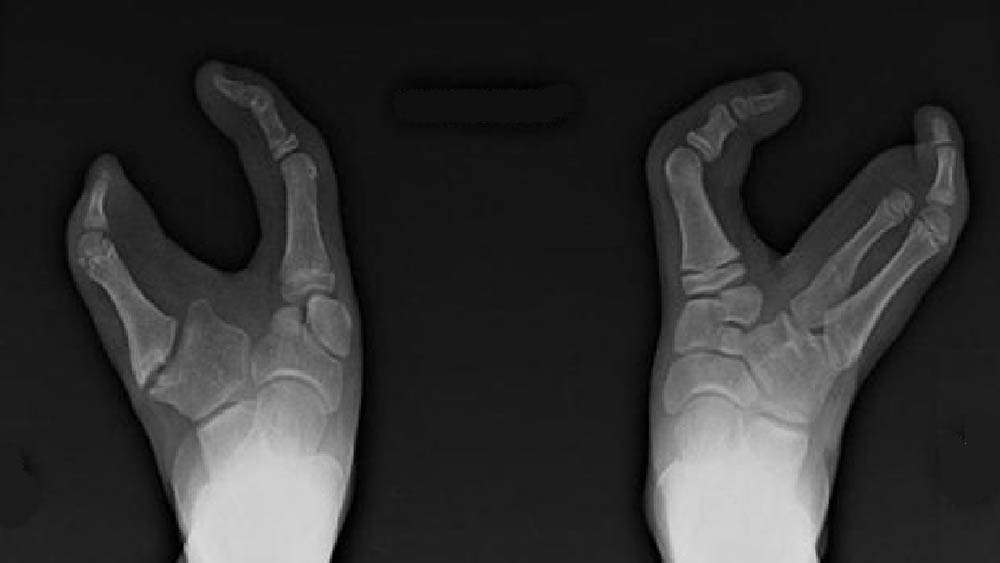

জিনগত কারণেই এই উপজাতি গোষ্ঠীতে জন্ম নেওয়া প্রতি চার জন শিশুর এক জনের পায়ের আঙুল দু’টি। এঁদের পায়ে বৃদ্ধাঙ্গুষ্ঠ এবং কনিষ্ঠা বাদে মাঝের তিনটি আঙুল অনুপস্থিত।

ভাদোমা উপজাতির মানুষদের যে দু’টি আঙুল আছে, সেগুলিও ভিতর দিকে ঢোকানো। পায়ের আকৃতি অনেকটা উটপাখি বা অস্ট্রিচের মতো। তাই অনেকেই এঁদের ‘অস্ট্রিচ পদবিশিষ্ট’ উপজাতি বলে থাকেন।

ভাদোমা উপজাতির প্রতিটি মানুষ ‘লবস্টার ক্ল সিনড্রোম’ নামক এক জিনগত রোগে আক্রান্ত। এই রোগে আক্রান্ত মানুষদের জন্মসূত্রেই পায়ে এক বা একাধিক আঙুল থাকে না।